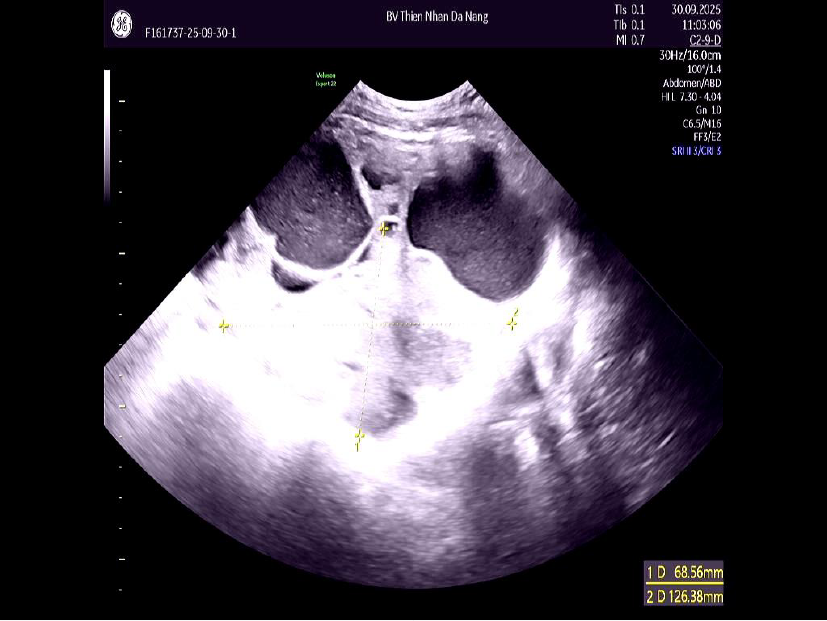

Đến cuối tháng 9/2025, khi xuất hiện đau bụng, chướng vùng rốn và ra huyết âm đạo kéo dài, chị T. đến Thiện Nhân Hospital thăm khám. Kết quả siêu âm ghi nhận khối u phát triển nhanh, kích thước 16–17 cm, chiếm gần trọn ổ bụng, tương đương với thai khoảng 6 tháng.

Kết quả MRI ghi nhận: Kích thước khối u: Buồng trứng trái có khối u 170mm, tăng nhanh so với 140mm chỉ sau 3 tháng. Đặc điểm hình ảnh: ORADS 5, mức độ nghi ngờ ác tính rất cao, cao hơn so với kết quả MRI trước đó (ORADS 4).